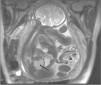

Describimos el caso de un hidromucocolpos diagnosticado en ecografía prenatal y confirmado por resonancia magnética (RM) prenatal como una masa retrovesical que secundariamente producía una ureterohidronefrosis bilateral que se resolvió con el tratamiento inmediato después del nacimiento.

Se trata de un recién nacido hembra de 39 semanas de gestación, de parto eutócico, cuyo peso al nacer es de 3.475g con test de Apgar al minuto de 9 y a los 5min de 10, con diagnóstico ecográfico prenatal de tumoración retrovesical de aproximadamente unos 45mm con ureterohidronefrosis bilateral. La RM fetal mostraba la presencia de probable hidromucocolpos por imperforación del himen con presencia de ureterohidronefrosis bilateral (fig. 1). La ecografía a las 12h de vida mostró la presencia de tumoración pélvica que corresponde a cavidad vaginal llena de líquido espeso, así como ureterohidronefrosis bilateral (fig. 2). A las 24h de vida se realiza himentomía, que da salida a abundante líquido lechoso y espeso. La analítica efectuada a las 48h de vida mostró unas cifras de urea, (15mg/dl) y creatinina (0,5mg/dl) dentro de límites normales. La exploración física, así como el resto de las exploraciones complementarias realizadas descartaron la presencia de otras anomalías anogenitales o urológicas.